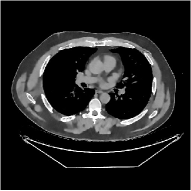

This section compares the generalization capabilities between the proposed MBIR method, PWLS-ST-, and a denoising deep NN, FBPConvNet [14], that are trained from the phantom data; in particular, we tested the trained PWLS-ST- and FBPConvNet models to phantom and clinical scan data. The results in Fig. 6 show that the non-MBIR FBPConvNet method has higher overfitting risks, compared to the proposed PWLS-ST- MBIR method. When tested on clinical scan data, PWLS-ST- achieves much more accurate reconstruction, compared to FBPConvNet. See Fig. 6(b). When tested on phantom data, FBPConvNet generates more unnatural features as the number of views reduces, although it gives lower RMSE values compared to PWLS-ST-. See zoom-ins in Fig. 6(a). The FBPConvNet results above correspond to those in the recent work [16] that FBPConvNet [14] generated some unexpected structures.